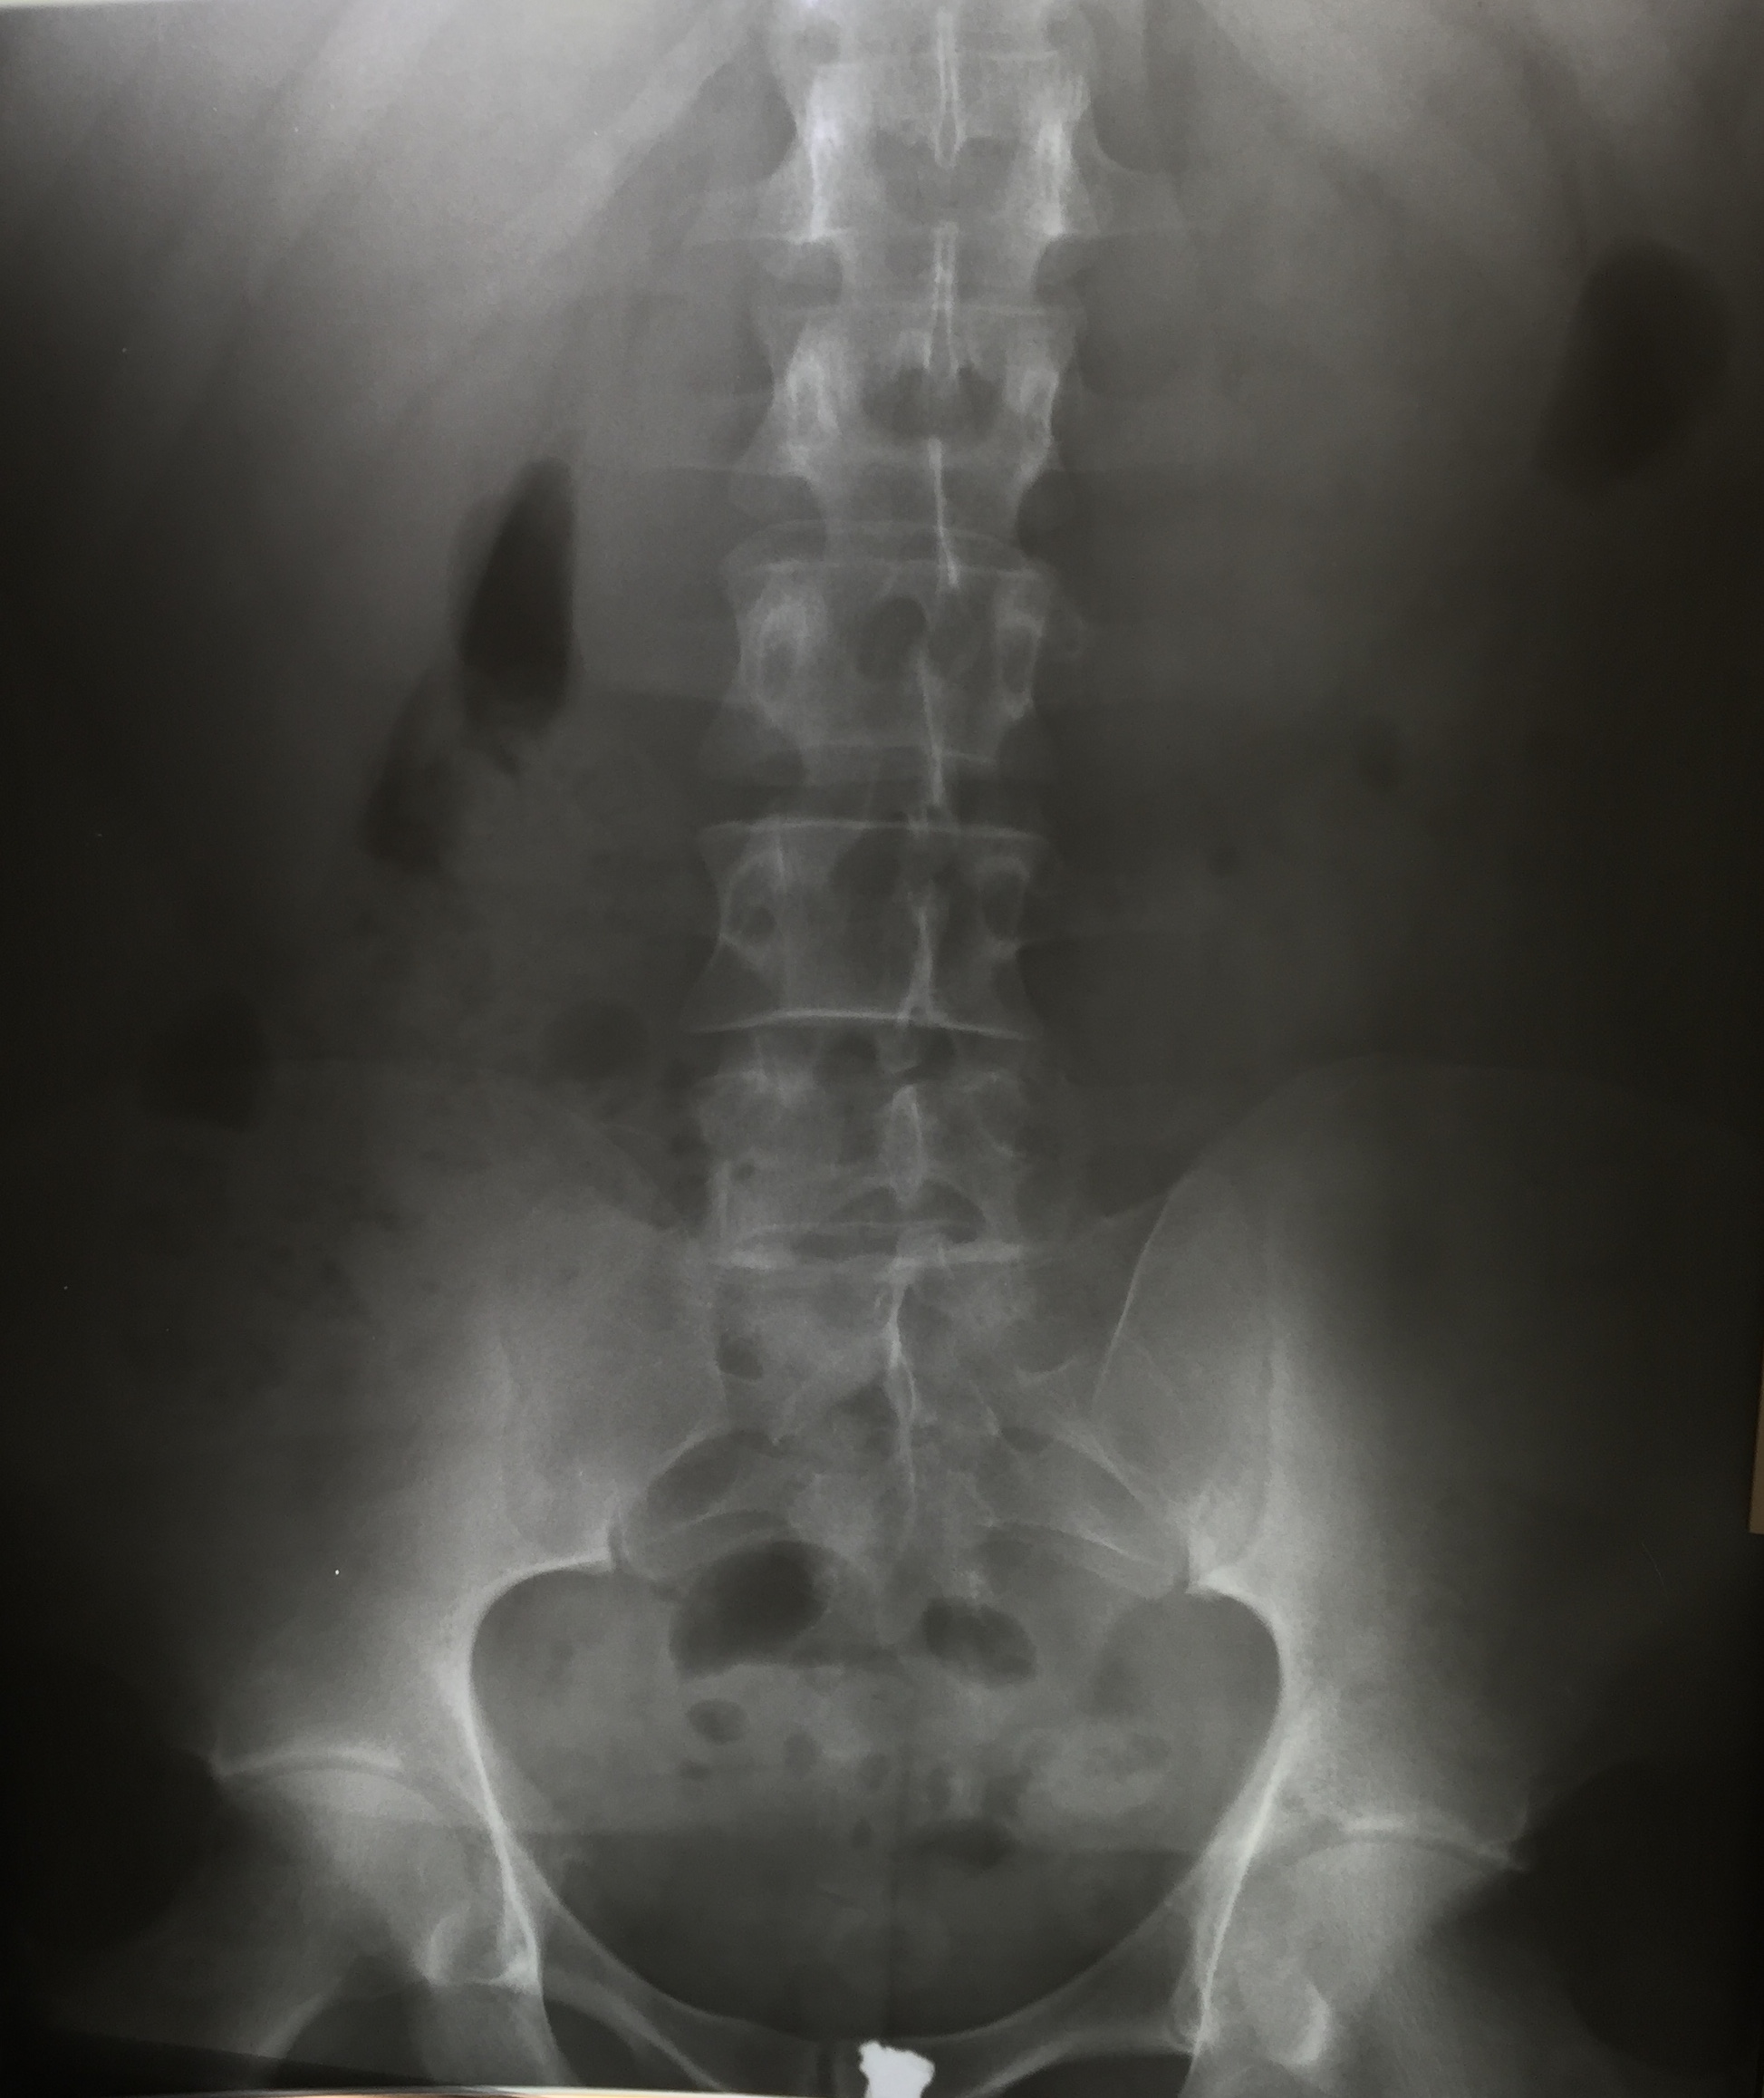

4. 1. 단순 X선 촬영

단순 X선 촬영은 물체를 X선 또는 기타 고에너지 형태의 전자기파에 노출시켜 생성된 잔류 빔(또는 "음영")을 잠상으로 포착하여 이미지를 생성하는 "투사 방사선 촬영"의 일종이다.[32] 뼈와 일부 장기(예: 폐)는 투사 방사선 촬영에 적합하며, 비교적 저렴한 검사로 높은 진단 수율을 보인다.[32] 뢴트겐이 X선을 발견한 이후, 의료 분야에서는 주로 뼈나 폐의 병변을 그려내는 영상 진단으로서 적극적으로 이용되어 왔다.

단순 X선 촬영의 주요 이용법은 다음과 같다.